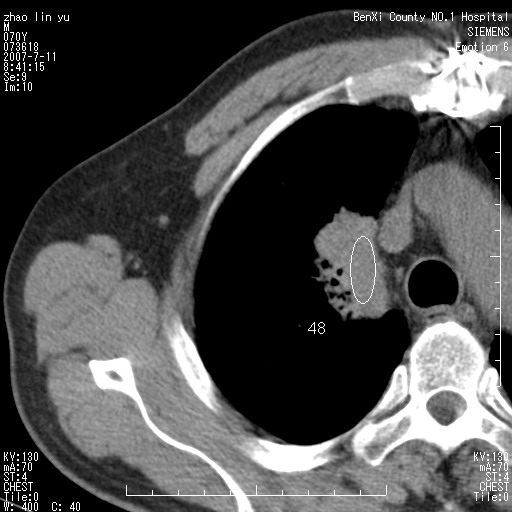

以下是引用王靖旗在2007-7-10 17:12:00的发言:[br] 男、70、咳嗽两个月,半年前换瓣手术,胸片未见异常,于昨天行x片发现右肺上野大片影,行ct扫描,这里是减薄图像,余肺正常。明天晚上会有增强扫描片,到时我会上传。[br][br] 冠状位请大家细看,应该是有意义的,[br][br] 请大家先看平扫发表意见。[br][br]

以下是引用zhangzhongshou在2007-7-10 21:43:00的发言:[br]右肺上叶周围型肺癌,以孤立型细支气管肺泡癌可能性大。